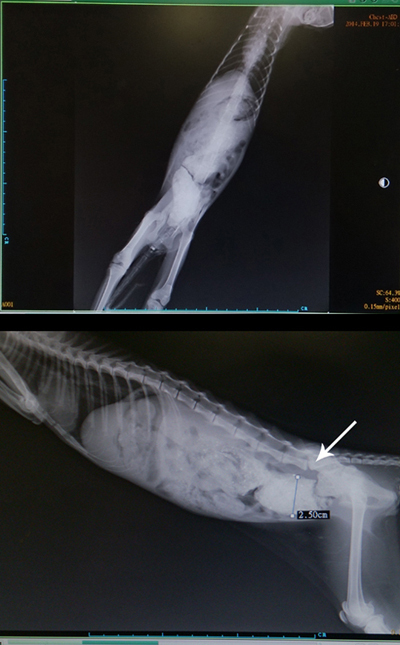

x光片可見腹部有很多糞便,

已非常硬,

擔心已成糞石,

趕緊替貓咪浣腸。

除了排便之問題,

x光片還可見骨盆骨折已癒合之情況,

尾椎部分也有受損,

猜測應該是之前有被撞過。

浣腸後注入顯影劑拍x光片,

腸道部分顯示寬度過大,

應是已被糞便撐大了。